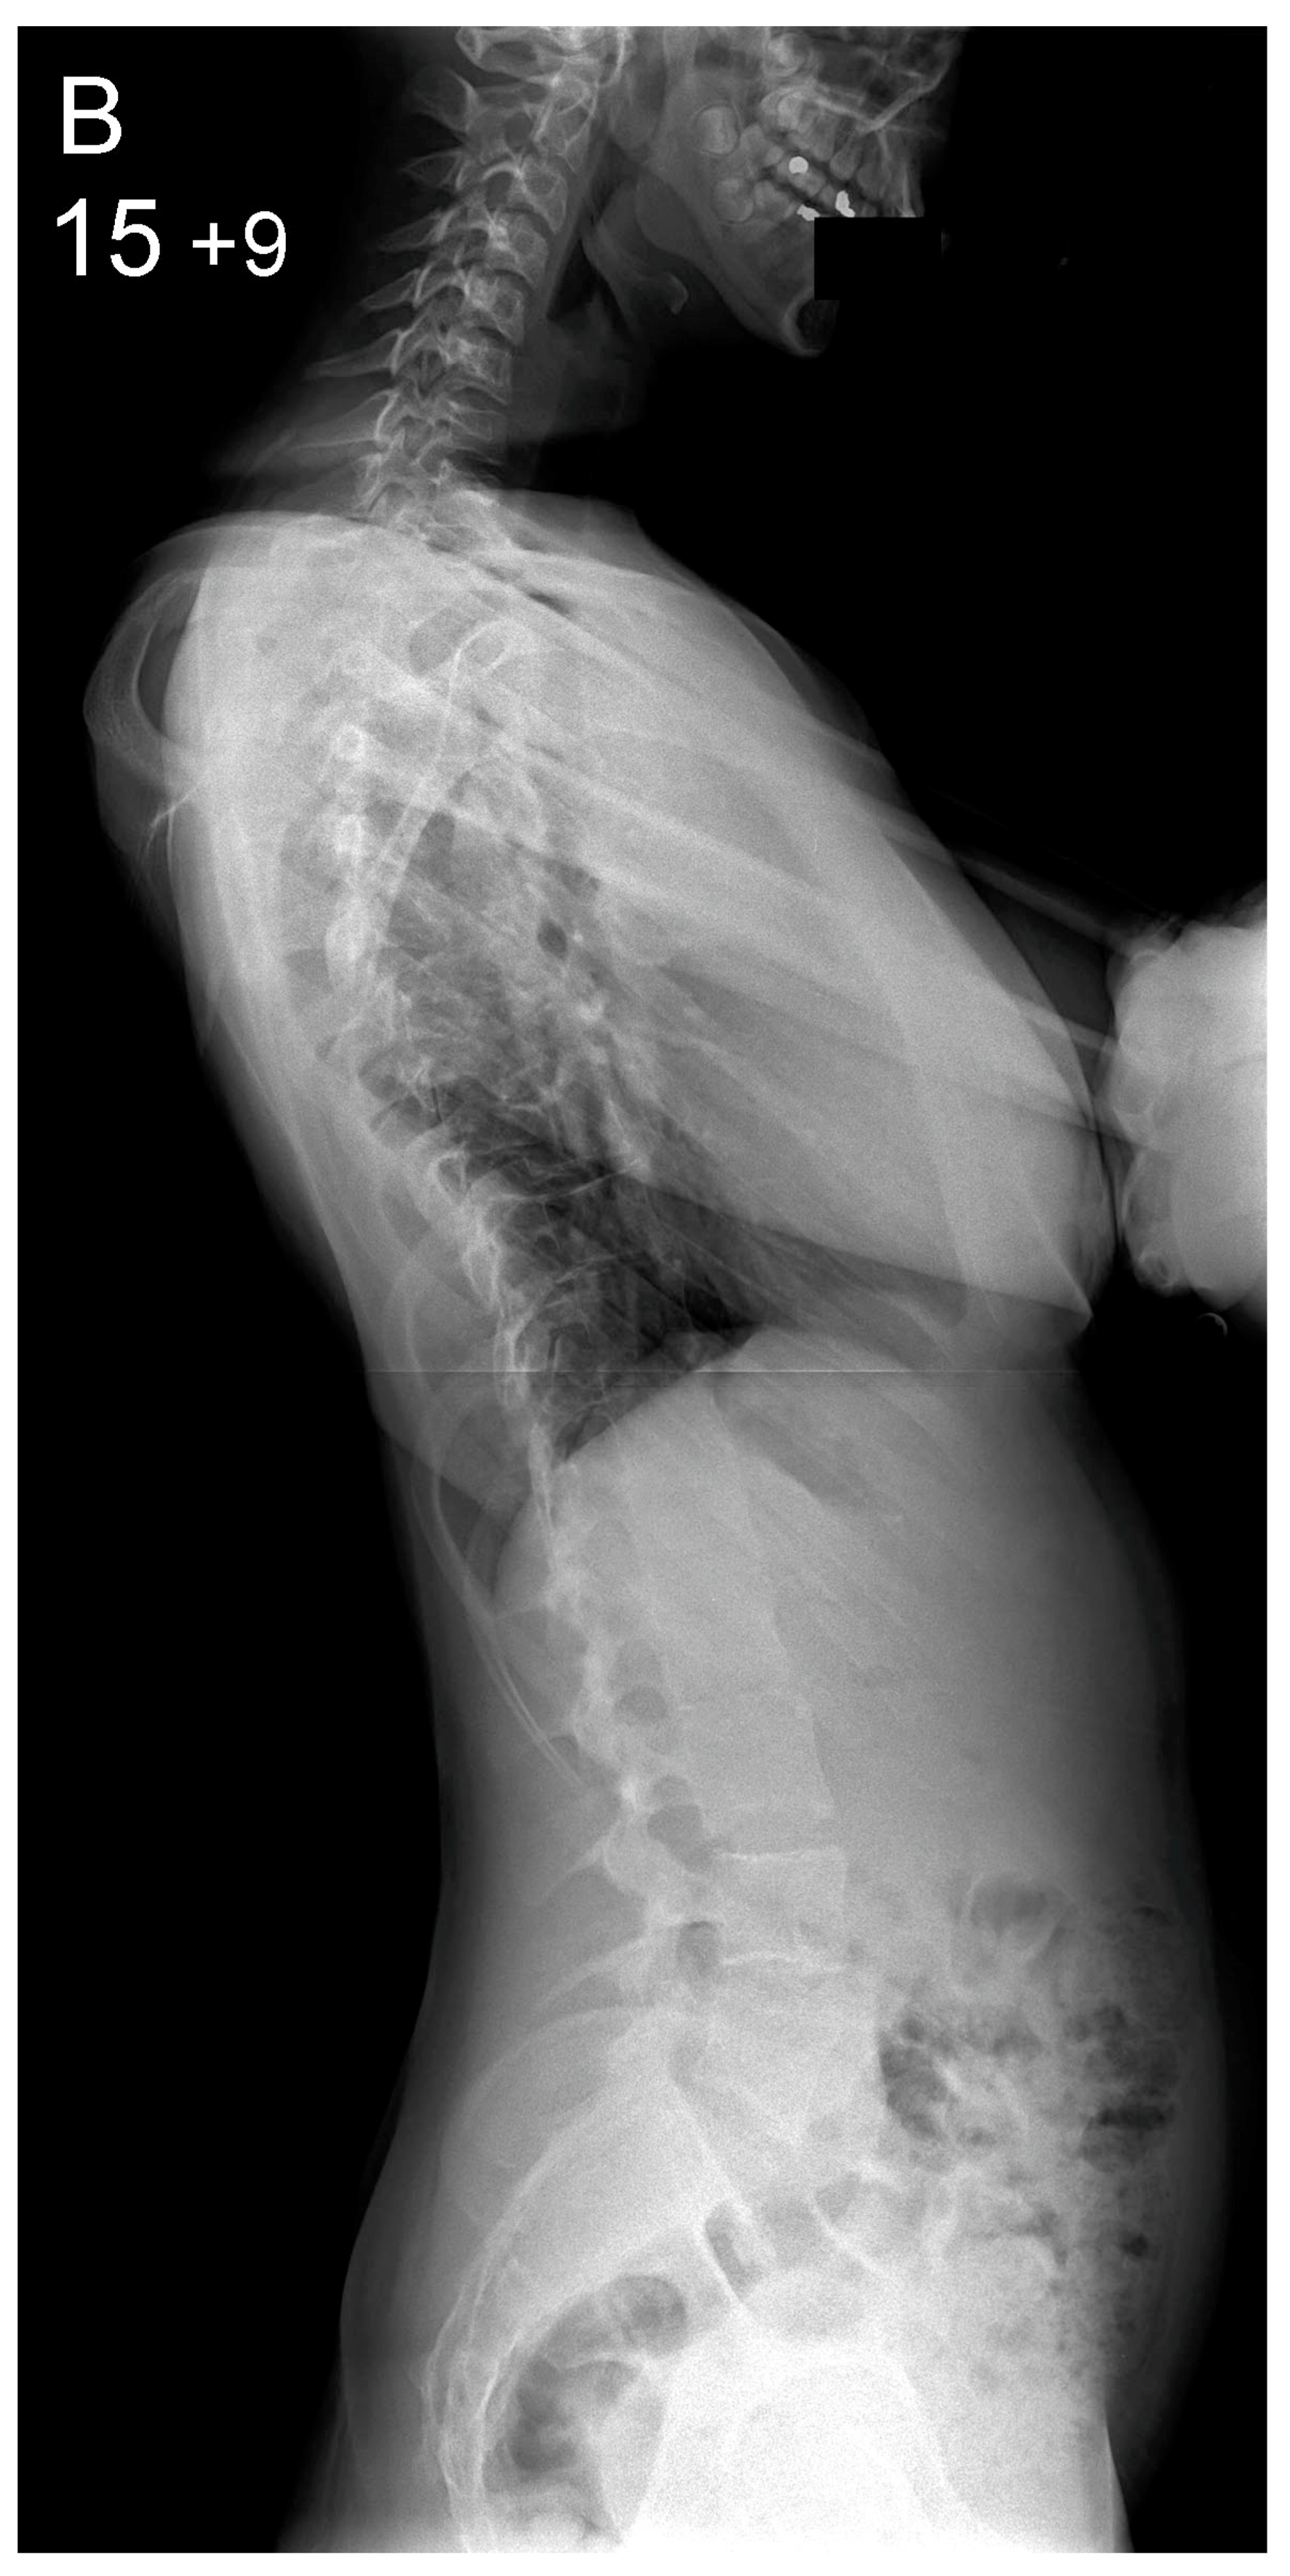

| Main thoracic scoliosis mean (range) | 64° (44–90) | 62° (42–94) | 0.31 | |

| Preoperative (°) | 64 (44–90) | 62 (42–94) | 0.31 |

| Thoracic Kyphosis | |||

| Preoperative (°) | 38 (3–80) | 31 (−17–65) | 0.01 * |

| Postoperative (°) | 42 (16–62) | 43 (30–58) | 0.2 |